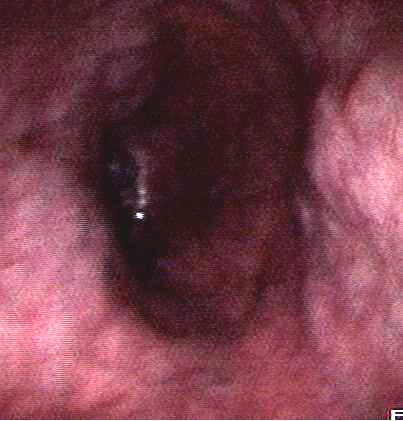

(三)、内镜下食管静脉曲张套扎术

我国是肝硬化大国,肝硬化并上大消化道出血是威胁生命最危险的并发症。该技术是在胃镜检查同时,直视下直接结扎引起出血的食管曲张静脉,简单、微创,不手术,效果显著。